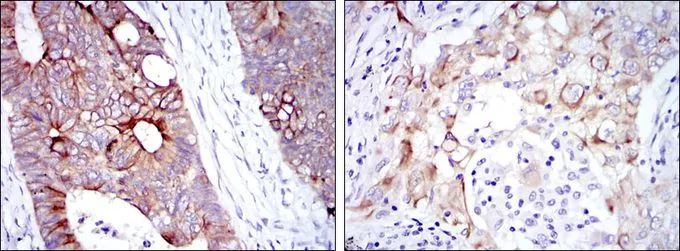

![IHC-P analysis of rectum cancer tissue (left) and lung cancer tissue (right) using GTX60457 Cytokeratin 19 antibody [1H6]. IHC-P analysis of rectum cancer tissue (left) and lung cancer tissue (right) using GTX60457 Cytokeratin 19 antibody [1H6].](https://www.genetex.com/upload/website/prouct_img/normal/GTX60457/GTX60457_20170912_IHC-P_w_23061123_461.webp)